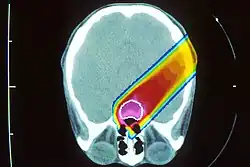

Прото́нная терапи́я является одним из видов корпускулярной терапии (Particle therapy), которая использует пучок протонов высокой энергии для облучения больной ткани, наиболее часто при терапии рака.

В сравнении с фотонами (гамма-излучение) или лёгкими электронами тяжёлые заряженные частицы, такие как протоны и ещё более тяжёлые ионы, при торможении в веществе имеют характерную особенность зависимости энерговыделения от, собственно, энергии: чем медленнее движется ион, чем меньше его энергия, тем больше её выделяется на единицу пройденного пути. Зависимость энерговыделения от пройденного пути имеет ярко выраженный пик Брэгга вблизи полной остановки частицы. Пробег протона в веществе определяется его энергией, которую можно подобрать с таким расчётом, чтобы пик пришёлся на облучаемую ткань.

Благодаря большой массе при ионизации (электромагнитном взаимодействии с электронами атомов) протоны испытывают слабое поперечное рассеяние в ткани, разброс длины их пробега также мал. Пучок можно сфокусировать на опухоль во всех трёх направлениях, минимизируя повреждения окружающих здоровых тканей. Энергия протонного пучка выбирается в диапазоне 70 до 250 МэВ, что соответствует пробегу в воде до 38 см, то есть позволяет облучать опухоль в любой части организма. Ткани, расположенные до Брэгговского пика, получают некоторую дозу, меньшую, чем опухоль в пике, и значительно меньшую, чем при облучении фотонами. Более того, эта доза может быть ещё уменьшена за счёт прецизионного вращения либо самого пучка вокруг пациента с помощью специального устройства гантри[2], либо вращения пациента при фиксированном пучке протонов. Ткани, расположенные за Брэгговским пиком, практически не получают ионизационной дозы.

Для равномерного облучения объёмных опухолей используется композиция протонов разной энергии, которые образуют так называемый модицифицированный пик Брэгга (SOBP — Spread Out Bragg peak).